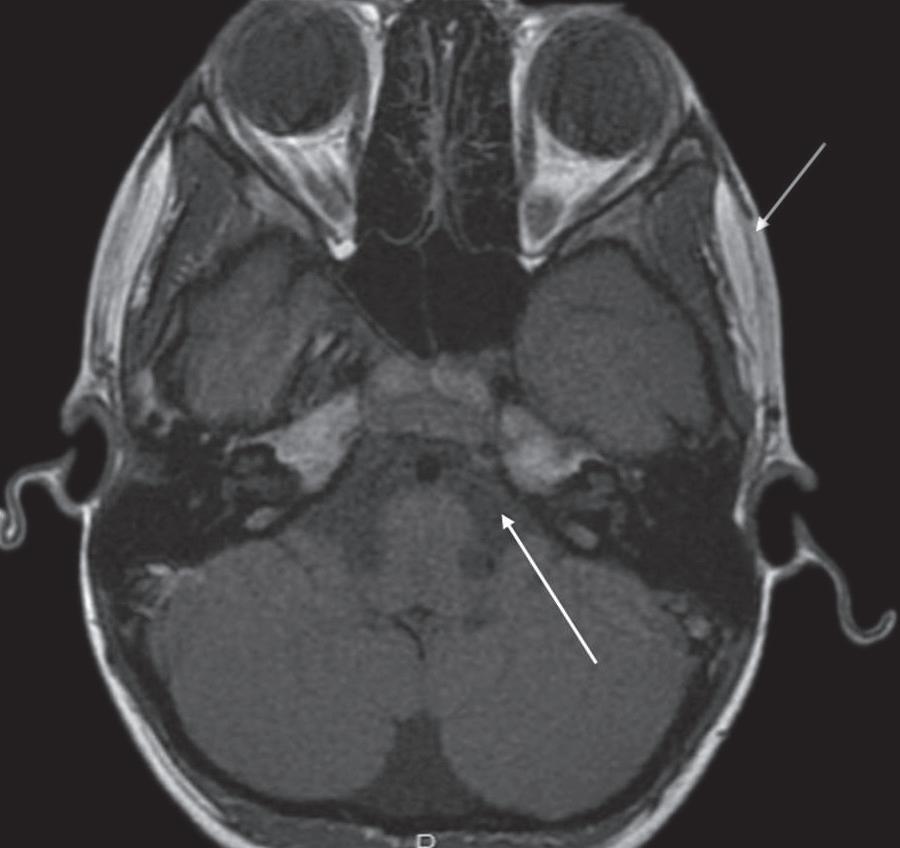

A sequência gradiente-eco balanceado steady state (FIESTA, CISS, TrueFISP) é uma sequência muito rápida, com aquisição volumétrica das imagens, adquiridas com espessura de corte muito fina e sem intervalo entre os cortes. Esta sequência demonstra conteúdo fluido de liquor, perilinfa ou endolinfa com sinal hiperintenso, com acurácia, estruturas neurais e a relação com estruturas vasculares na fossa posterior (Figs. 1-12 e 1-13).

1-12. Sequência volumétrica. Sequência axial volumétrica: liquor com sinal hiperintenso (seta curta), sétimo e oitavo nervos cranianos na cisterna do ângulo pontocerebelar (seta longa).